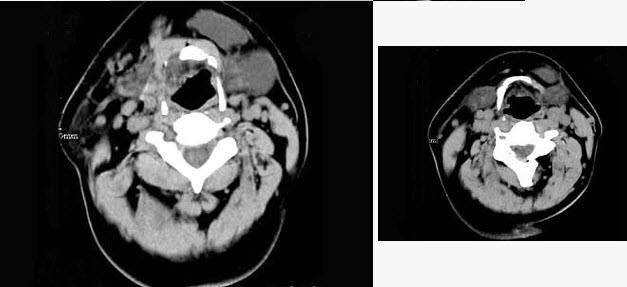

扁桃體惡性腫瘤圖片

扁桃體癌圖 (69)